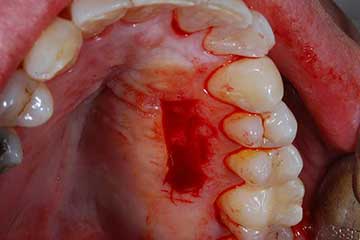

IMPIANTI POST-ESTRATTIVI

I denti irrecuperabili dell'arcata superiore ed inferiore del paziente di anni 65

sono stati sostituiti da 10 impianti, cioè protesi radicolari endo-ossee che sostengono le protesi fisse superiore ed inferiore.